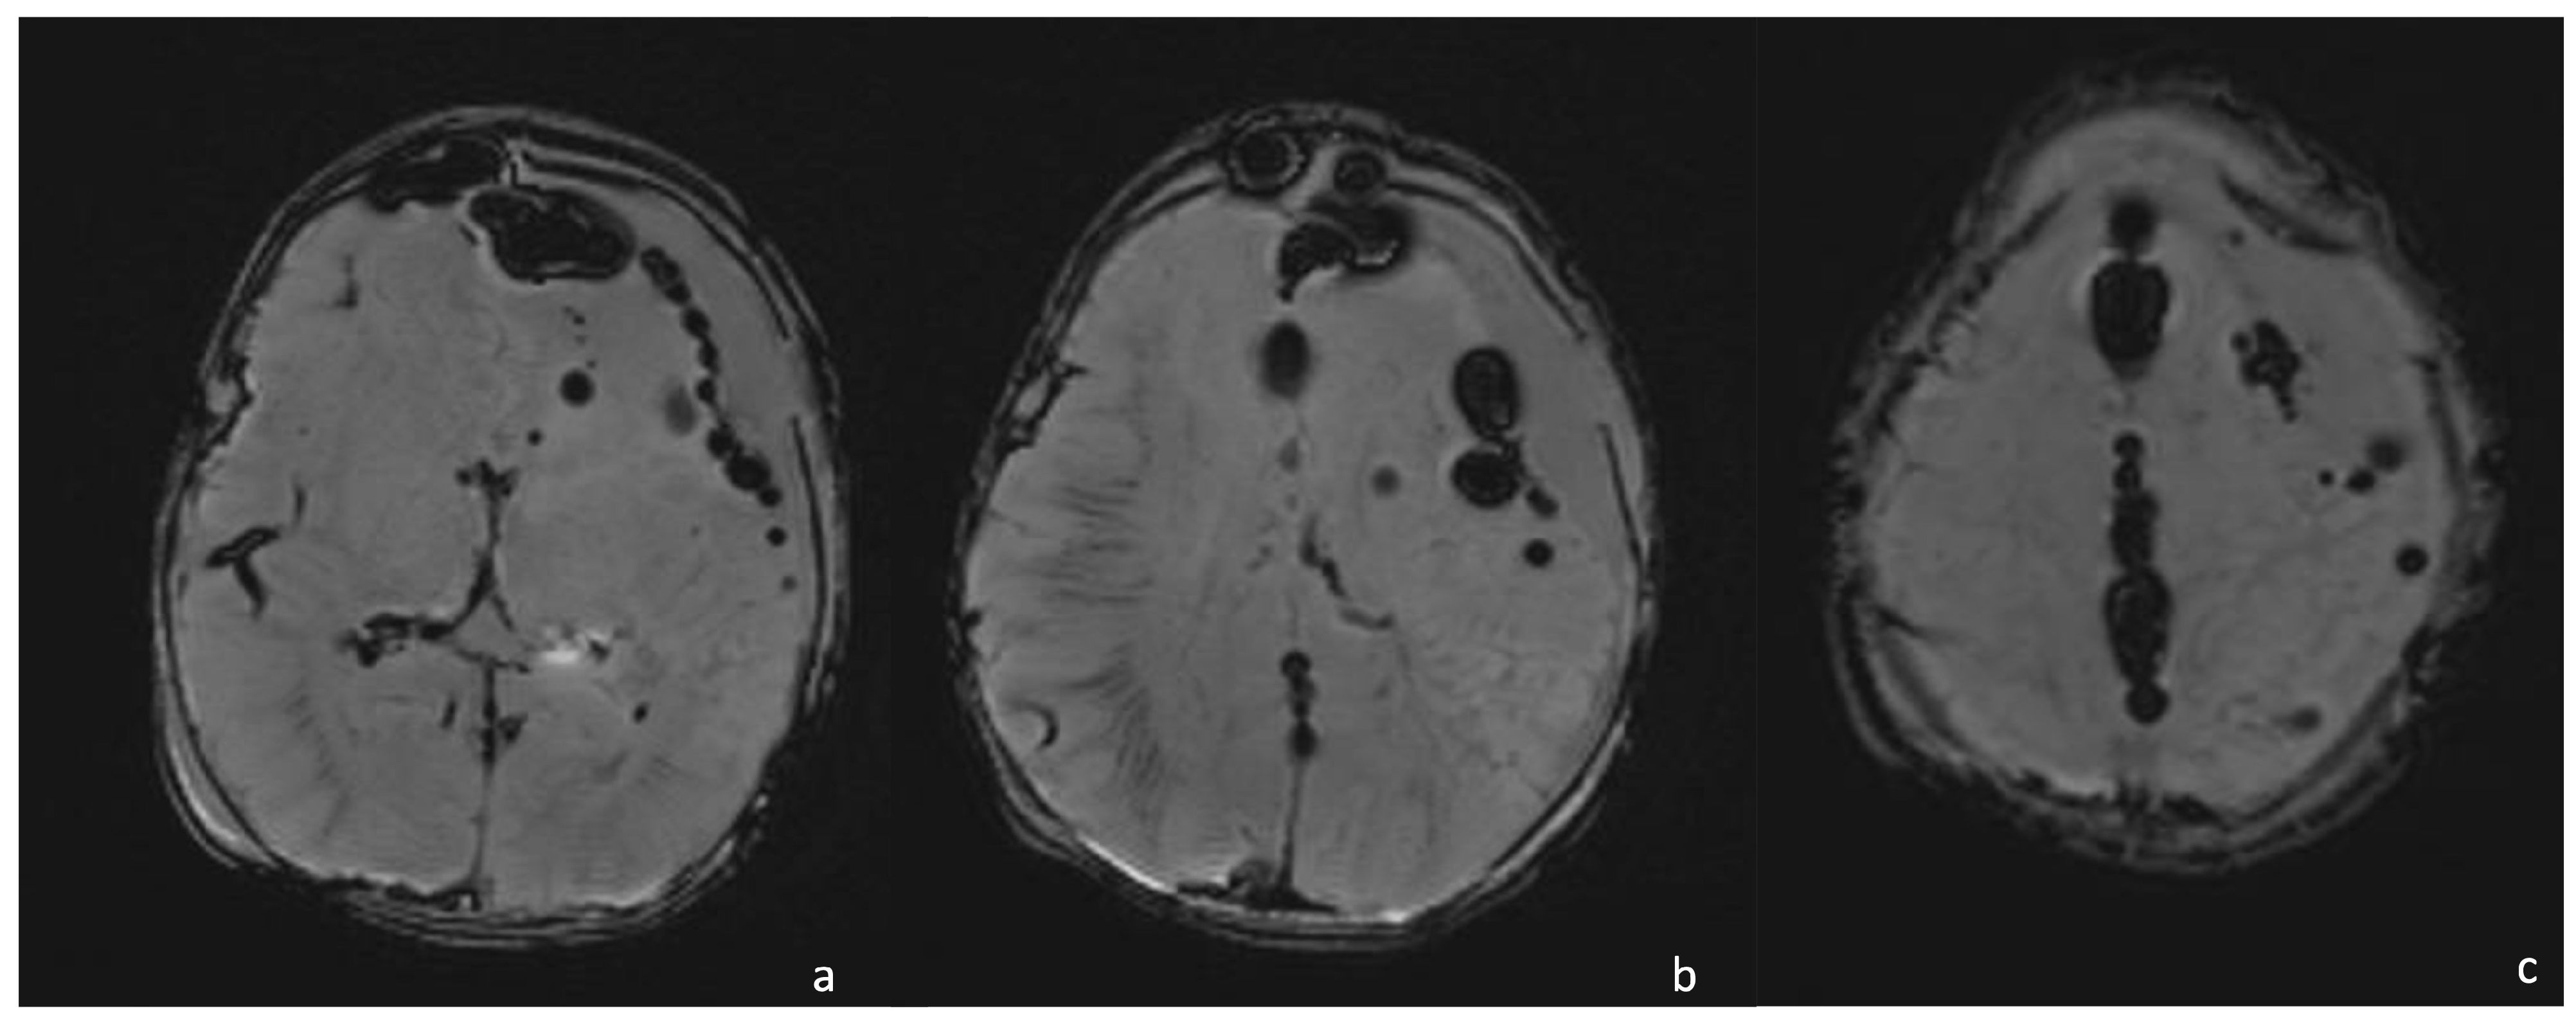

7.3. Gram-Negative Bacteria and Abscesses

- Late capsule formation (weeks to months): The parenchymal abscess presents a necrotic core, appearing hypointense on T1WI and hyperintense on T2WI with diffusion restriction on DWI/ADC. The capsule is inhomogeneously thick, appearing thicker towards the cortex and thinner towards the ventricles, appears isointense on T1WI and hypointense on T2WI, and presents an intense enhancement. On the US, the abscess presents a well-defined hypoechoic core and a complete hyperechoic rim, pairing CT that shows a well-defined hypodense core and a complete peripheral enhancement.

- Late cerebritis (5–14 days): Cerebritis progressively evolves to show a necrotic core and an initial encapsulation. This stage flows into and partly overlaps with the early capsule stage since this last represents a progression with similar, yet more advanced features of the late cerebritis stage. In MRI, the late cerebritis results in a focal formation characterized by a necrotic core, appearing inhomogeneous on both T1 and T2WI, without a complete and regular contrast peripheral enhancement, yet with a defined diffusion restriction on DWI/ADC. On the US, the appearance is similar to the early cerebritis, yet the lesion appears more focal and the core starts becoming hypoechogenic, similar to CT showing a significantly hypodense core in the lesion with irregular and incomplete peripheral enhancement. Early capsule formation (14–30 days): The cerebritis is becoming an abscess since the capsule is evident, yet it is incomplete and thin and appears as a hyperintense rim on T1WI and a hypointense rim on T2WI with contrast enhancement on T1WI.

- Early capsule formation (2 weeks to 2 months): the lesion presents diffusion restriction on DWI/ADC, mainly in relation to hypercellularity. Sonographically, the lesion presents a well-defined hypoechoic core and an incomplete hyperechoic rim. CT shows a well-defined hypodense core and an incomplete peripheral enhancement.